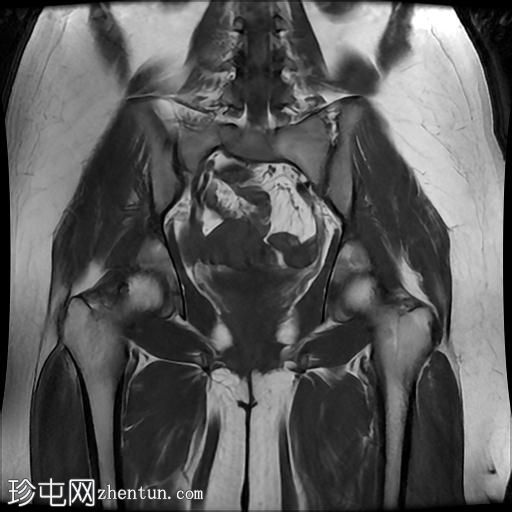

MRI

轴位

T1加权像

冠状位

臀中肌髂骨起点处前侧全层撕裂,伴有充满液体的间隙,以及髂骨髓水肿。

MRI结果符合臀中肌近端髂骨起点处全层撕裂的

影像

学表现。